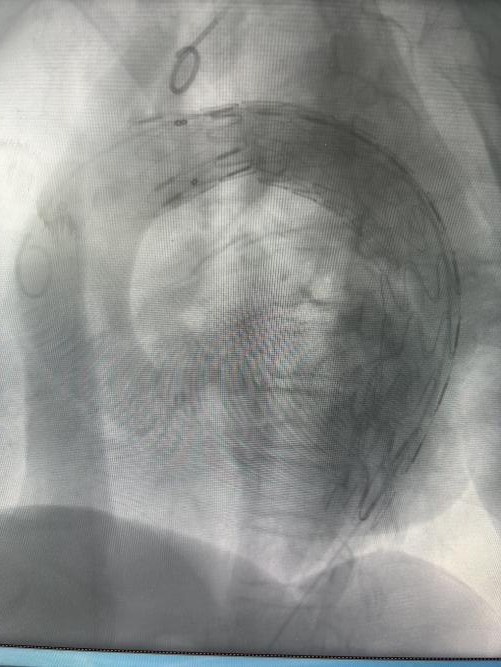

术前 术后

与此同时,在介入导管室护士长孙宁及其团队护理骨干张琨、赵康和技师郑红云的默契配合下,薛松教授团队骨干、上海仁济医院心血管外科副主任医师刘冀东,徐州一院心脏大血管外科执行主任、医学博士单江桂和副主任医师王峦通力协作,精准定位夹层破口,在DSA引导下将覆膜支架精准送至夹层破口处。随着支架成功释放、假腔血流消失,手术顺利结束。